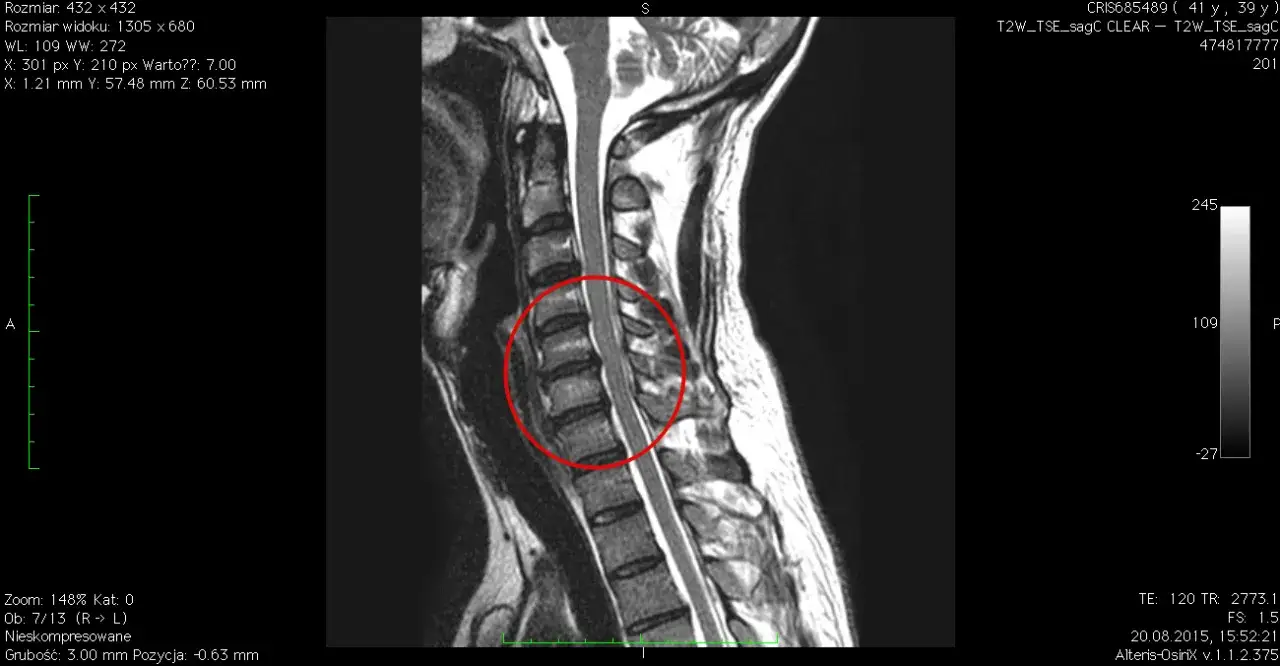

Proces diagnostyczny rozpoczyna się od szczegółowego wywiadu lekarskiego. Następnie przeprowadzane jest badanie fizykalne, podczas którego lekarz ocenia zakres ruchów szyi, siłę mięśniową oraz czucie w kończynach górnych. Kluczową rolę w diagnostyce odgrywają badania obrazowe.

- Rezonans magnetyczny (MRI) - pozwala dokładnie zobrazować tkanki miękkie, w tym krążki międzykręgowe i nerwy

Interpretacja wyników badań

Prawidłowa interpretacja wyników badań jest kluczowa dla postawienia trafnej diagnozy. Pozwala ona określić dokładną lokalizację i stopień zaawansowania zmian chorobowych. Rolą specjalisty jest zestawienie obrazu klinicznego z wynikami badań, co umożliwia opracowanie optymalnego planu leczenia.